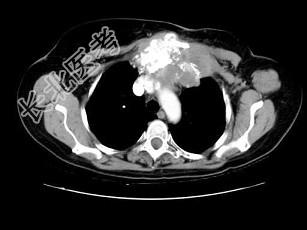

- 单项选择题女,46岁, 胸痛,乳腺癌放、化疗术后, 结合图像,最可能的诊断是 ( )

B、胸骨坏死